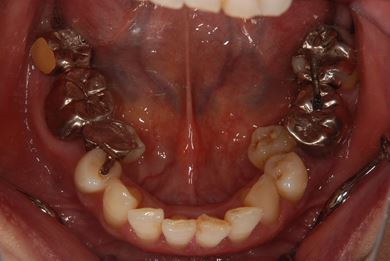

抜歯即日スピードインプラント治療+セラミック治療

| 性別/年齢 | 女性 / 49歳 | ||||||||||||||||||||||||||||||||

| 主訴 | 左奥歯のつめものが取れている所を治療したい。 | ||||||||||||||||||||||||||||||||

| 治療方針 | 抜歯と同時にインプラント埋入を行い、治療期間を短縮する。上前歯部、骨再生法によりインプラント治療を可能にする。 | ||||||||||||||||||||||||||||||||

| 治療内容 | インプラント4本(抜歯即日スピードインプラント、テンポラリーインプラント+仮歯)、メタルボンドセラミックブリッジ12本、メタルボンドセラミッククラウン3本(メタルボンド用土台1本) | ||||||||||||||||||||||||||||||||